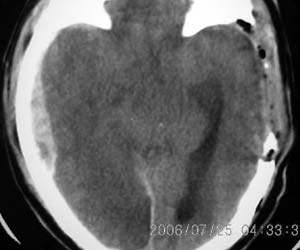

以下是引用lushijun在2006-7-25 21:02:00的发言:[br]1、双侧枕叶脑挫裂伤 2、硬膜下血肿 3、蛛网膜下腔出血[br]

以下是引用同在2006-7-25 21:11:00的发言:[br]双侧枕叶脑挫裂伤 硬膜下血肿 蛛网膜下腔出血

以下是引用kbzyycm在2006-7-25 22:54:00的发言:[br]1、双侧枕叶脑挫裂伤 、硬膜下血肿 蛛网膜下腔出血.[br]